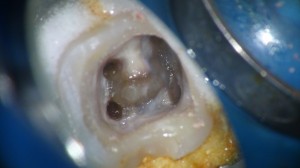

金属の冠を外すと中はかなり感染しておりました。

その部位を削合しながら窩洞の内面を整理し、歯を補強するとこんな感じ